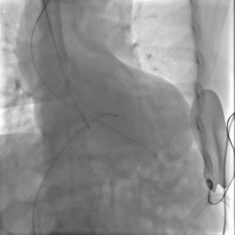

根部造影